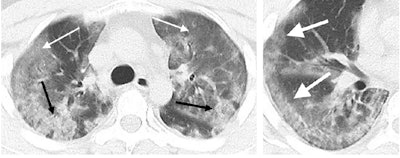

After analyzing the patients' imaging data, Chung and colleagues recognized that the most common CT findings were bilateral ground-glass opacities and consolidative pulmonary opacities, which were present on the scans of all patients with an abnormal CT scan. The only patients whose scans did not show one of these two types of opacities were the three patients who had entirely normal CT scans at presentation.

Three secondary CT findings helpful for early diagnosis were nodular opacities (33% of patients), a peripheral distribution of disease throughout the lungs (21%), and a crazy-paving pattern (19%).

In addition, there was no evidence of lung cavitation, discrete pulmonary nodules, pleural effusions, or lymphadenopathy in cases of 2019-nCoV. Follow-up CT scans demonstrated mild or moderate disease progression, as indicated by increasing extent and density of lung opacities, in roughly 88% of the patients.